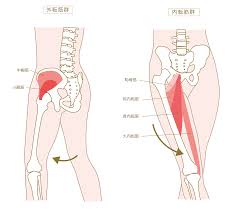

太ももの内側には、大内転筋、長内転筋などの股関節内転筋群という筋肉群があります。内転筋は股関節を内転させる、股を閉じる動きに関わる筋肉で、3層の筋肉層によって構成されています。

第1層(表層)は恥骨筋・薄筋・長内転筋の3つの筋肉があります。第2層(中間層)には短内転筋があります。第3層(深層)には大内転筋・小内転筋があります。これら3つの筋肉を内転筋群と言います。内転筋群に痛みを感じた場合、炎症を起こしている状態は内転筋群炎症になります。